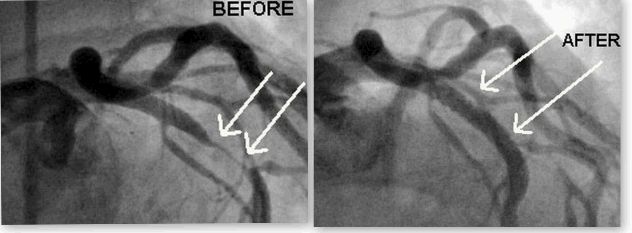

The angiograph strips below were taken during my stenting procedure. The radiation dose for an angiogram is mostly dependent on the time and energy used to obtain the results. Some procedures can be done in minutes others take longer. i.e. stenting. So depending on the procedure and size of the person of course the radiation doses for angiographs can range anywhere from 10-100 times more that a CTA in some cases. LATEST NEWS ON IMAGING, BIO ABSORD STENTS ETC. CAN BE FOUND here Shown below is photo of my main LAD before and directly after my stent, May28, 2013. Below photos where taken during the my stent procedure catheterization - angiography - angioplasty procedure Stents and Positive remodeling, Dr Srinivas explains. might be a good place to start especially if your Calcium score is high?

< CLICK ON PHOTO TO SEE THE SAME ARTERY PRE-CATH ON A CTA |

Right Photos are my arteries and are links, yikes! What does artery disease look like on a CTA? A 2017 CTA photo of my arteries: The left photo unfortunately shows the current disease in the CFX artery. My recent radiological report from these photos mentions coronary artery disease only and depicts the stenosis within the artery as a percentage, mine is < 25% great, but this is only a guesstimate and can vary 10% 20% and up to 30% is my understanding. I have seen two cardiologists since with the radiological report and they both say great less than 25%, blockage while neither actually even bothered to look at the photo with the actually disease. I asked both doc's if they would like to see the photos and they both declined. The Stenosis reported in the above angio photo group (BEFORE / AFTER) at the time of the stent was reported as 40% 50% and 60% by angio cath and now by CTA they say < 25%, I am in the process of finding out by comparison if this is true, I will be comparing the 2013 CTA to the 2017 CTA. By observation I noticed the overall sublumenal disease show in photos has not seemed to change much if at all. I also learned that the angio photo guesstimates are just that and do not hold much weight as far a accuracy if at all, they appear to be visual guides with numbers attached by the surgeon and or helper at the time of the CATH, why bother except to sell more operations. So in 2013 my artery blockages were 40-50-60% determined by the angiogram now compared to a CTA they are less than 25%, yea right, wishful thinking for sure. The disease looks the same to me photos to be posted. Can't help thinking that they do many unnecessary by pass operations based on the CATH readings/photos which are at best only guesstimates in most cases. i.e. I recently had a friend diagnosed by CATH that he had 80% blockages is all four arteries and received an immediate quadruple by bass operation? When you go under you basically give them cart blanche to do what is necessary, the way I got around this was to get the CTA before the CATH, In my case I was pretty sure what was going to happen before the CATH.

HOMOCYSTEINE LEVELS ARE OVERLOOKED BY ALMOST ALL CARDIOLOGISTS, YET IT REMAINS A GREAT & SIGNIFICANT FACTOR IN HEART DISEASE ! THE TEST COSTS UNDER $50 My homocysteine level was almost 17 when the above Before After pictures were taken, now it is 8. Genetic tests revealed that I am homozygous For A1298C which is a predictor of High Homocycteine. See B12 absorption page dangers of high homocysteine and Coronary Heart Disease and why don't they tell people! |